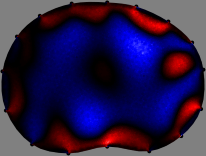

Figs. 3 and 4 compare the performance of the proposed FER method in (20) with the standard regularized least-squares method ((19) when \mathcal{R} is the identity matrix). The regularization parameter of the standard method was heuristically chosen for its best performance, and the parameter of the FER method was set to be one of three different values λ=0.05,0.2,𝜆0.050.2\lambda=0.05,0.2,\infty. The injection current was 1 mARMSRMS{}_{\tiny{\mbox{RMS}}} at 100 kHz, and the frame rate was 9 frames per second. The reference frame at t0subscript𝑡0t_{0} was obtained from the maximum expiration state. The measured data, 𝐕˙(tm)˙𝐕subscript𝑡𝑚\dot{\mathbf{V}}(t_{m}), represent the voltage differences between each time tmsubscript𝑡𝑚t_{m} and t0subscript𝑡0t_{0}. The blue regions, which denote where conductivity decreased by inhaled air, increased during inspiration and decreased during expiration. The FER method with λ=𝜆\lambda=\infty was clearly more robust than the standard method that produced more artifacts originated from the inversion process.

Figure 4: The reconstructed images of the conductivity change of the subject B by the standard regularized least square method and the proposed fidelity-embedded regularization (FER) method for three difference values λ=0.05,0.2,𝜆0.050.2\lambda=0.05,0.2,\infty. Here, the time step is 0.55 seconds (tm+5tm0.55subscript𝑡𝑚5subscript𝑡𝑚0.55t_{m+5}-t_{m}\approx 0.55).